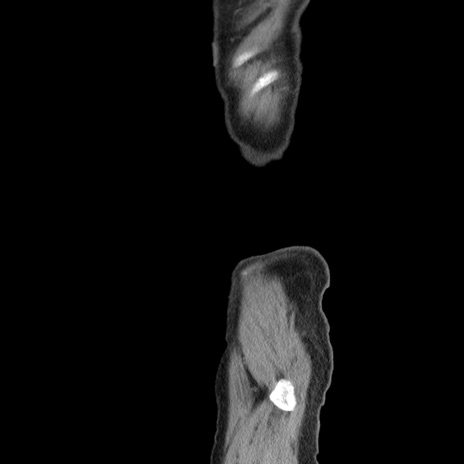

症例24(矢状断像)

横断像